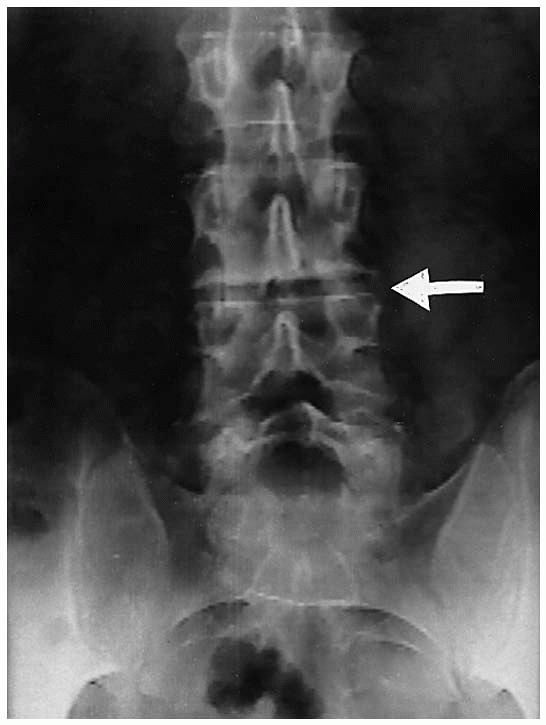

![]() |

FIGURE 19-4. Preoperative anteroposterior x-ray film. L3-4 disc space collapse (arrow).

confirm the correct vertebral level or levels of fusion and to localize

the incision. Anteroposterior (AP) and lateral radiographs (Figs. 19-4 and 19-5), as well as axial computerized tomography (CT) or magnetic resonance imaging (MRI) (Figs. 19-6 and 19-7)

Plain radiographs, in the anteroposterior and lateral projection, of

osteophytic changes (Figs. 19-4 and 19-5). Restoration of the disc space height was achieved with an ALIF using a femoral ring allograft as a structural support (Fig. 19-29). Postoperative radiographs demonstrate the final pedicle screw construct for a one level fusion (Fig. 19-30).